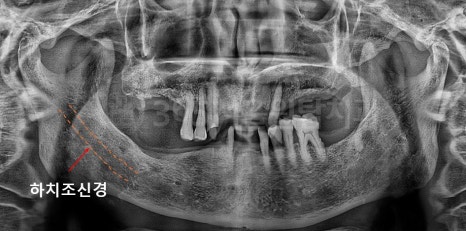

아래턱에는 하치조신경 이라는

큰 신경관이 지나가고 있습니다.

하악 임플란트 수술 진행 시

이 신경과의 거리를

정확히 확인하지 않으면

수술 후 저림이나

감각 이상이 생길 수 있습니다.

CT를 통해

• 신경의 정확한 위치

• 임플란트가 들어갈 수 있는

안전한 깊이를

미리 계산합니다.

임플란트는 한 번 심으면

되돌릴 수 없기 때문에

안전을 전제로 한 계획이

무엇보다 중요합니다.